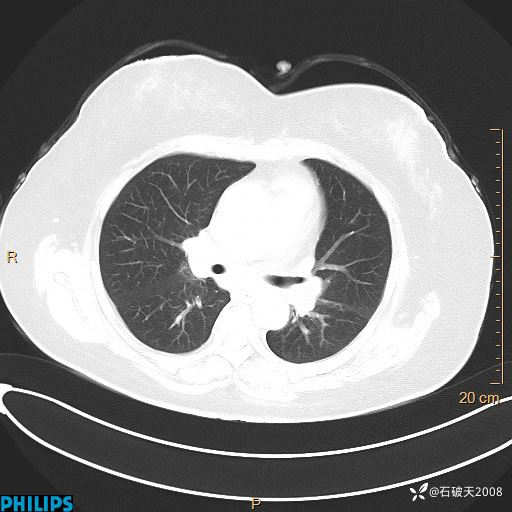

肺结节病?纵膈型肺癌?淋巴瘤?有点意思,欢迎围观

女 52岁 主 诉:咳嗽10余天,咳痰2天。

现病史:10余天前无明显诱因出现咳嗽,呈阵发性干咳,伴咽喉部发痒,无咽痛,无咳痰,无鼻塞、流涕、打喷嚏,无发热、畏寒、寒颤,无头痛、头晕,无胸闷、胸痛,无反酸、烧心,无腹痛、腹泻,无尿频、尿急,无皮疹等,在当地诊所求治,给予口服药物治疗(具体不详),病情无好转。遂在当地社区卫生服务中心开具口服药物治疗(具体不详),疗效欠佳。2天前出现咳痰,在我院门诊求治,行胸部CT提示肺部感染,建议住院,患者要求口服药物治疗,目前仍咳嗽、咳白色粘痰,白天量多,夜间自觉喉部喘鸣音,遂再次来院就诊,以“肺部感染”为诊断收入院。发病以来,神志清,精神可,饮食可,夜间睡眠差,大小便正常,近期体重无明显变化。

动脉期

静脉期